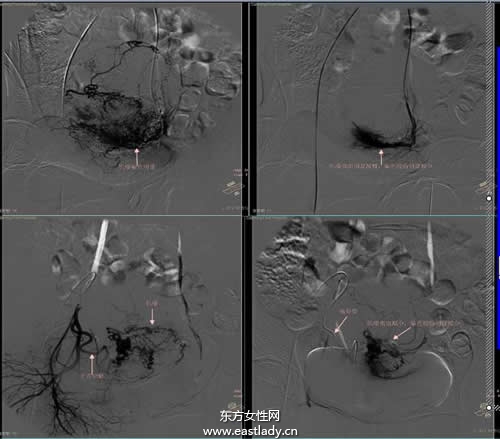

1.介入治療:介入治療就是在X線電視、CT、B超引導(dǎo)下,將特制的穿刺針、導(dǎo)管插入肝臟的腫瘤區(qū)進(jìn)行診斷及治療的一種方法,多以肝動(dòng)脈化療栓塞術(shù)為主體,療效較好,且發(fā)展也很快,所以身體素質(zhì)較好的肝癌晚期患者可選用此種治療方法。